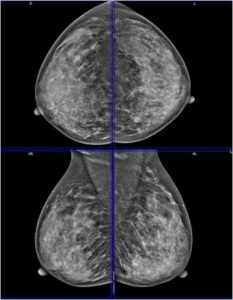

43 year female patient has come for routine screening mammogram.